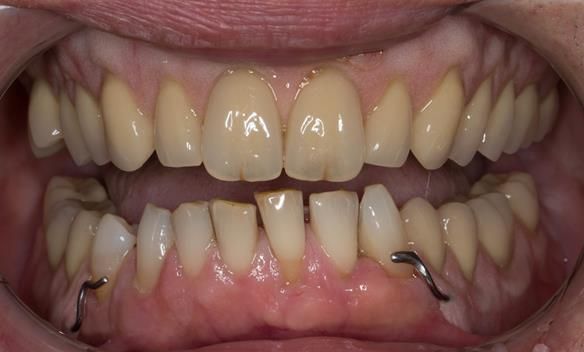

- Definitive dentures (Mk 2) – complete upper metal reinforced and lower cobalt chromium based partial of hygienic Scandinavian design to be made 9 - 12 months after extractions of all upper teeth and LR5 and LL4

The clinical situation and treatment process is shown in detail below with photographs.

The patient has been successfully rehabilitated and is now having periodontal maintenance from Syed Abad, Specialist in Periodontics at the practice. His quality of life has improved considerably. The clinical prosthodontics was provided by me and the technical work by Rowan.